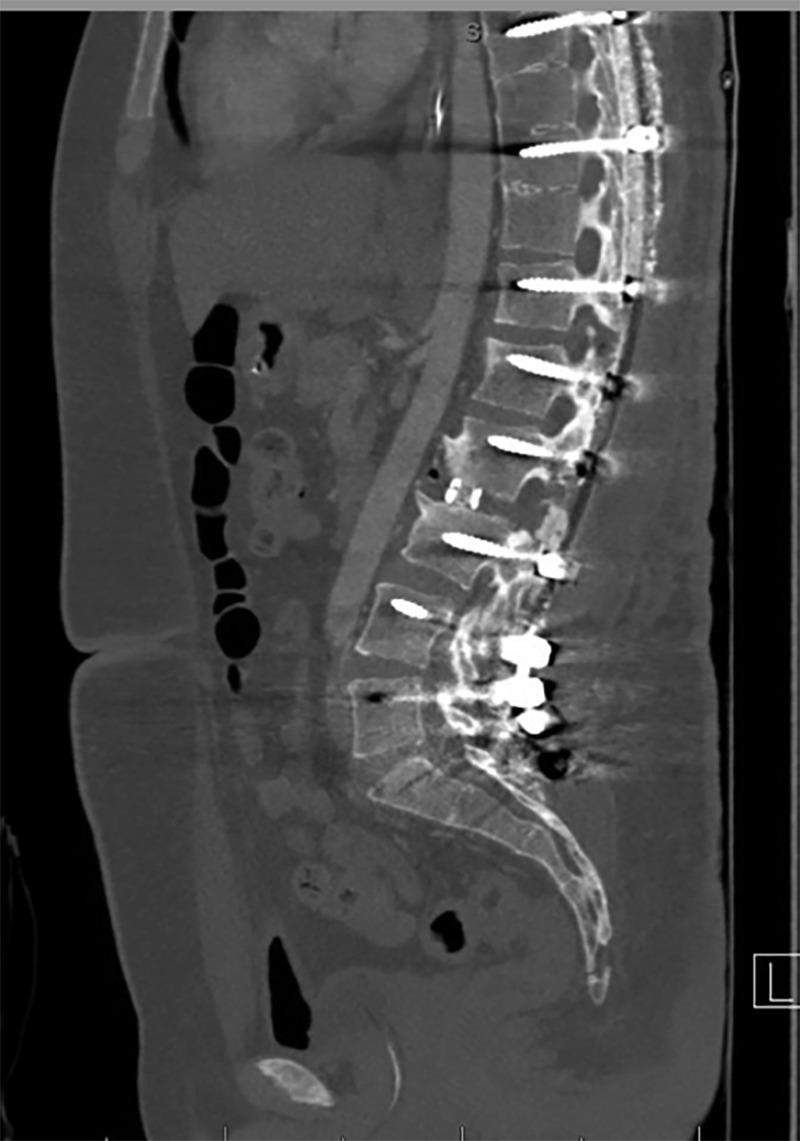

A 24-year-old man presented with progressive back pain and a fixed severe thoracolumbar kyphosis centered at the L2-L3 disc space seven years after removal of instrumentation for intractable infection following correction of Scheuermann's Kyphosis. The patient also demonstrated pseudoarthrosis of the posterior thoracolumbar fusion bed. The original operative plan was to perform a vertebral column resection (VCR) of L2 to correct his severe kyphosis.  During preparation for the VCR, the patient's deformity corrected completely after insertion of blunt distraction paddles for the interbody fusion after the Ponte osteotomy at L2-L3. A VCR was avoided, and the construct was able to be completed with simple rod insertion and posterolateral fusion.

RESULTS

The described technique achieved 69 degrees of correction at the L2-L3 disc space without any remodeling of the surrounding vertebrae. The C7 plumb line was normalized, and the patient was able to stand upright with horizontal gaze and without pre-existing discomfort. At the six-month follow-up, the patient reported a significant improvement in pain and was able to resume normal activities.